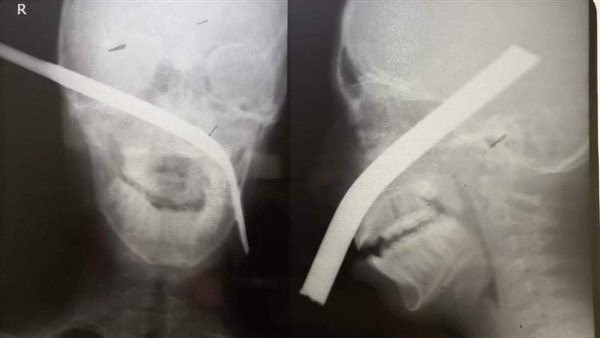

استخراج سيخ حديد اخترق وجه طفل في المنيا